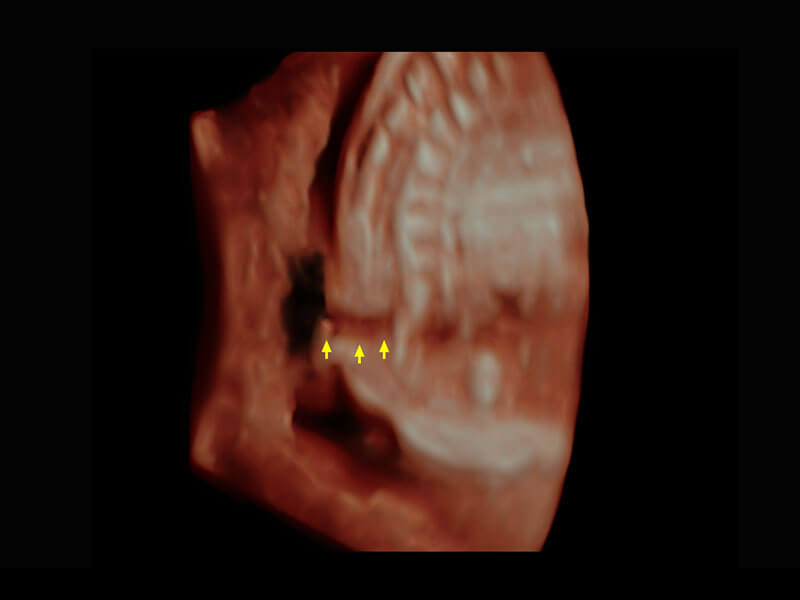

盆底超声

P60为盆底超声检查提供应用方案,多种腔内及腹部容积探头提供从二维、三维到四维的优异图像品质,实时快速三维容积数据获取,专业的测量工具包等人性化设计,为超声医生诊断提供有力保障。

S-Pelvic

能够简化盆底检查的操作流程,可在二维模式及三维成像模式下实现一键自动提取出标准切面、自动识别当前切面、自动测量,提升盆底检查的高效性,同时也能让青年医生快捷的获得准确的检查结果。